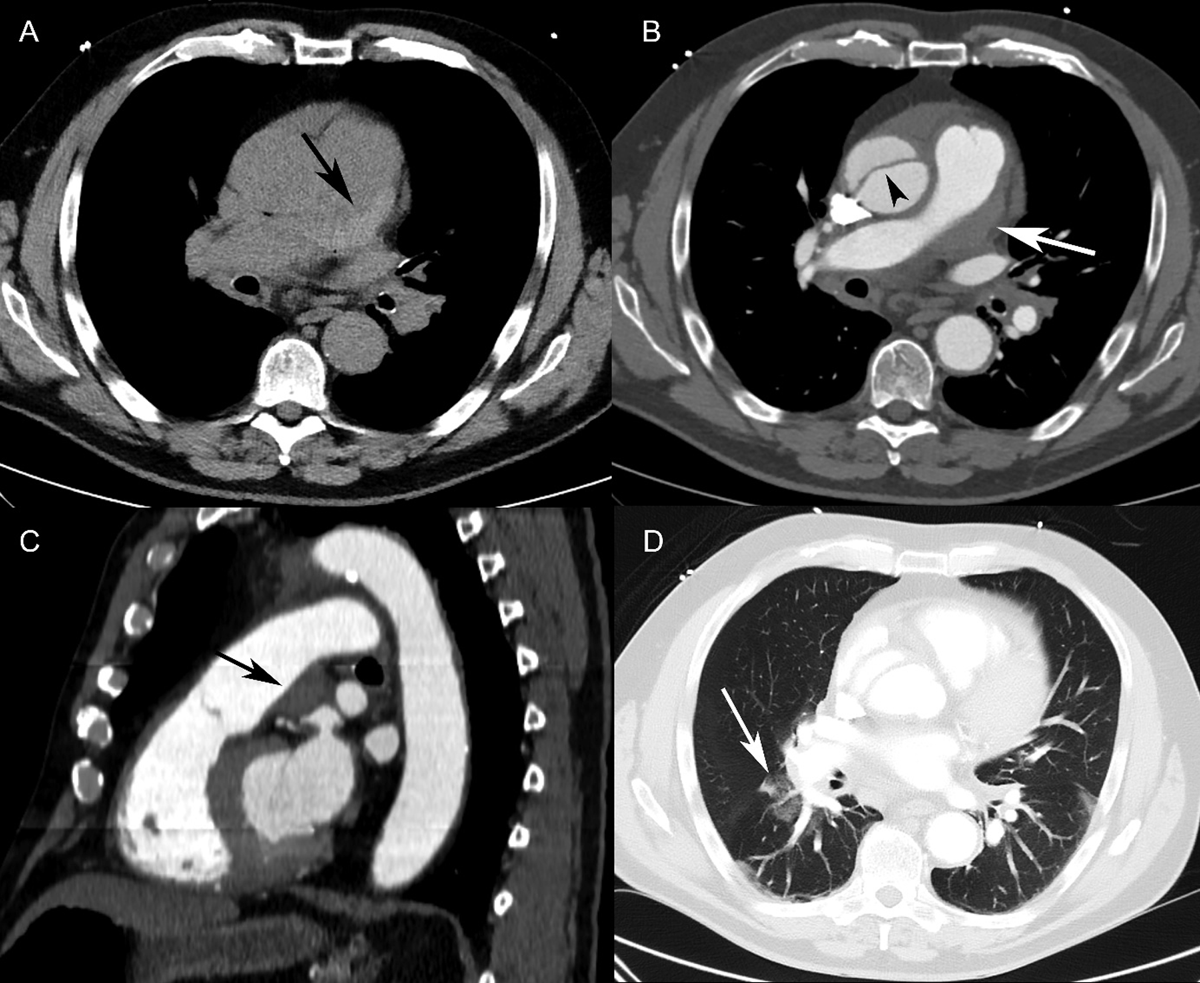

Figure 2

Patient 2. (A) Axial non-contrast-enhanced CT showed a hyperdense lesion along the pulmonary trunk wall (black arrow). (B) Contrast-enhanced CT (axial view) revealed an eccentric hypodense defect in the pulmonary trunk (white arrow), mimicking a mural thrombus. The intimal flap was seen in the ascending aorta (arrowhead). (C) Sagittal reformatting of a contrast-enhanced CT scan revealed a lesion with well-defined margins at an obtuse angle (black arrow) along the pulmonary trunk wall, resulting in a slight narrowing of the pulmonary trunk lumen. This was not enhancing, suggestive of an intramural hematoma. (D) Axial CT (lung window) showed patchy ground-glass opacities in the right lower lobe around the segmental pulmonary arteries, consistent with alveolar hemorrhage.